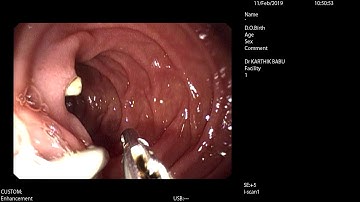

ERCP - Stone Extraction using a Stone Extraction Balloon - EndoFlex GmbH - EN